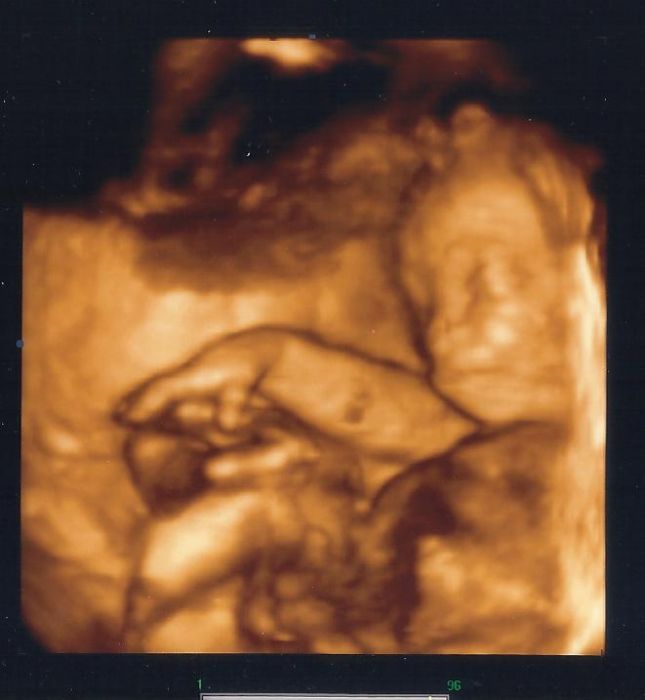

Naskenovala jsem fotečku pinďourka, ale není nic moc, už je veliký

11.9.2012 v 20:39

[203628] příště prosím zakroužkovat, kde to "pohlavíčko" je

na těchhle fotkách vidím většinou jen rozmazaný skvrny

[203631] no pinďourek není vidět, strašně sebou vrtěl a už nejde zachytit celej, pořád měl nožičky u hlavy, no prdloušek

a všude placenta a voda, ta první byla lepší no, ale tahle je taky krásná, je krásnej...po mně

[203628] zajímavá fotečka, když se člověk zadívá tak to vypadá jak kdyby tam byli do konce i dvě miminka